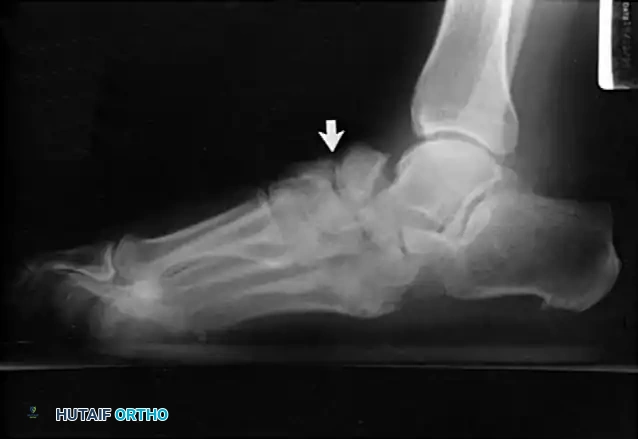

* Type 1 (Midfoot): Involves the tarsometatarsal (Lisfranc) and naviculocuneiform joints. This is the most common pattern, affecting approximately 60% of patients. It frequently results in a rocker-bottom deformity.

FIXED DEFORMITIES IN THE DIABETIC FOOT Surgical Diagram

If an ulcer is driven purely by a localized bony prominence in an otherwise stable foot (Eichenholz Stage III), a simple exostectomy may suffice. The most common site is the plantar-medial aspect of the midfoot (prominent medial cuneiform or base of the first metatarsal). Care must be taken to resect enough bone to relieve pressure without violating the remaining stabilizing ligaments, which could trigger a secondary collapse.

Lateral subluxation of the forefoot on the midfoot is the most common presentation of Type 1 Charcot. This produces an abducted forefoot, secondary hindfoot valgus, and a contracted Achilles tendon. Surgical correction involves a medial utility incision, resection of the destroyed TMT joints, realignment of the medial column, and rigid fixation using robust hardware (beaming screws, locking plates) or circular external fixation.